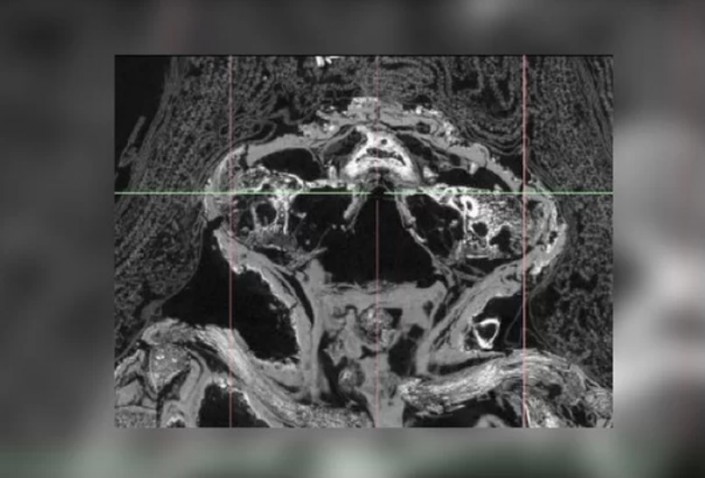

Открыв эту аномалию, работники музея связались с Нельсоном и его коллегами, специалистами в области компьютерной микротомографии. Ученые просветили мумию при помощи сканера и смогли увидеть даже самые мельчайшие ее детали, которые рассказали им о том, кто на самом деле был погребен под слоем позолоченного папируса и тканей.

Внутри ее "савана" команда Нельсона нашла тело недоношенного ребенка, умершего примерно на 26-28-й неделе после зачатия. Причина его смерти была очень простой - он страдал от анэнцефалии, полного отсутствия мозга. Сегодня подобные генетические дефекты поражают каждого десятитысячного младенца, подавляющее большинство которых гибнет еще до рождения.